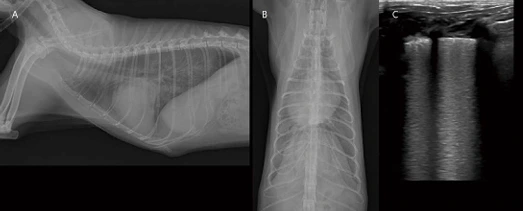

image.png?type=w966

8살 중성화 수컷 Scottish straight cat 5kg 환자가 노력성 호흡, 기력 저하로 내원하였습니다. 흉부방사선 검사에서 severe globoid cardiomegaly가 관찰됩니다. 외측상에서 심음영 전방으로 폐전엽으로 가는 폐혈관들이 얇게 관찰됩니다. Pulmonary hypoperfusion 상태로 고려됩니다. 소량의 흉수 및 patchy한 폐침윤 소견도 관찰됩니다(A, B). 심초음파에서는 다량의 심낭수가 관찰됩니다. 이로 인한 RA collapse, RV collapse, CVC plethora, 소량의 흉복수도 관찰됩니다(F, G). Cardiac tamponade 상태로 생각되어 매우 천천히 조심스럽게 심낭수 천자를 실시하였습니다(D). 심낭수는 transudate로 확인되었습니다. 심낭수 천자 후 환자는 일시적으로 호흡이 안정되었으며, 어느 정도 심낭수가 제거된 이후 심초음파에서 RA, RV collapse 소견은 개선되었습니다. Diffuse LV hypertrophy, severe LA dilation, smoke in the LA and Lau 등의 소견이 관찰되어, feline cardiomyopathy(hypertrophic phenotype)와 이로 인한 만성 다량의 심낭수, 소량의 흉수, 경등도의 심원성 폐부종, thromboembolism 상태로 임상적 가진단 하였습니다. 그러나 환자는 심낭수 천자 약 30분 이후부터 호흡 곤란이 심해졌고, 흉부방사선 검사에서 심한 acute pulmonary edema 진행되었습니다. 환자는 응급중환자실에서 적극적인 응급 처치를 시도하였지만, 객혈, 호흡 정지까지 빠르게 진행하였고, CPCR에 반응을 보이지 않고 사망하였습니다.

지난 시간 개의 심장/심낭막 질환 증례 보고에서도 있었던 Pericardial decompression syndrome (PDS) 발생 증례입니다. 이는 심낭천자술 후 발생할 수 있는 paradoxical 혈역학적 악화로 정의되며, 드물지만 치명적인 합병증입니다. 사람에서도 정확한 병태생리학은 알려져 있지 않지만, 혈역학, 허혈성, 자율신경계 불균형과 관련된 여러 메커니즘이 제시되어 있습니다(Yougeesh Prabhakar, Amandeep Goyal, Nauman Khalid, Nitish Sharma, Raj Nayyar, David H Spodick, and Lovely Chhabra. Pericardial decompression syndrome: A comprehensive review. World J Cardiol. 2019 Dec 26; 11(12): 282–291). 사람에서의 논문에 따르면, 심낭액을 제거한 후 정맥 환류 증가로 인한 우측 챔버 확장이 좌심실 충전 및 유효 심박출량에 영향을 줄 수 있고, 동시에, 전신 혈관 저항이 커짐에 따라 폐정맥 환류가 증가하면 부하 전후 불일치가 발생하여 울혈성 심부전이 발생할 수 있습니다. 추가 기여 요인으로는 심낭내압 증가가 최대 충혈 관상동맥 흐름에 영향을 미치는 것으로 알려져 있기 때문에 관상동맥 관류 장애로 인한 심근 허혈 및 기절이 있을 수 있습니다. 마지막으로, 삼출액 제거 후 교감신경 자극의 급격한 감소는 자율신경 불균형을 유발한다는 가설이 있습니다. 이러한 불균형은 순환 카테콜아민이 증가한 고아드레날린성 상태에서 명백하지 않았던 기존 심근 기능 장애가 압도적인 자율 신경 스트레스에 이차적으로 새로운 심근 기능 장애가 유도되기 때문에 발생하는 것으로 생각되고 있습니다. 이러한 PDS 위험 증가와 관련된 임상 요인에는 악성 질환, 방사선 치료 병력, 수축기 기능 저하를 동반한 기존 심근병증, 결합 조직 장애 등이 보고되어 있습니다. PDS의 발생 시기는 심낭 배액 후 환자의 혈역학이 일시적으로 초기 개선된 직후부터 며칠 이내로 다양하다고 보고되어 있습니다. 가장 일반적으로 폐부종을 동반한 급성 울혈성 심부전으로 나타납니다. 특별한 치료법도 예방법도 현재까지 입증된 바가 없으며, 다만 심초음파를 보면서 cardiac tamponade가 미약하게 완화될 정도까지만 심낭수를 매우 천천히 제거하는 것을 추천하고, 특히 종양 관련 삼출 또는 유의적 수준의 심실 dysfunction 환자에서 다량의 심낭수가 있을 경우 주의해야 합니다. 지난번 개의 증례는 종양 전이로 인한 다량의 심낭수 환자였고, 이번 고양이 증례는 심실 dysfunction이 있는 고양이 심근병증에서 다량의 심낭수 환자이므로, 심낭수 천자 시 위험 인자가 높은 상태였습니다. 그럼에도 불구하고 둘 다 심각한 cardiac tamponade였으므로, 심낭수 천자가 반드시 필요한 상태였습니다. PDS를 인지하고 매우 천천히 천자를 진행하였으나, 일시적 호흡 상태 회복 이후 짧은 시간 내로 사망하였습니다. 임상적으로 드물지만, 치명적일 수 있기 때문에 보호자 동의 및 충분한 설명이 필요합니다.